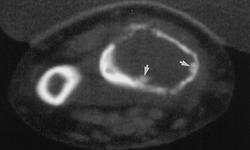

Гигантоклеточная опухоль.

Злокачественная гигантоклеточная  опухоль возникает из доброкачественной (частота 10-20%). После операции возможно появление рецидива опухоли.